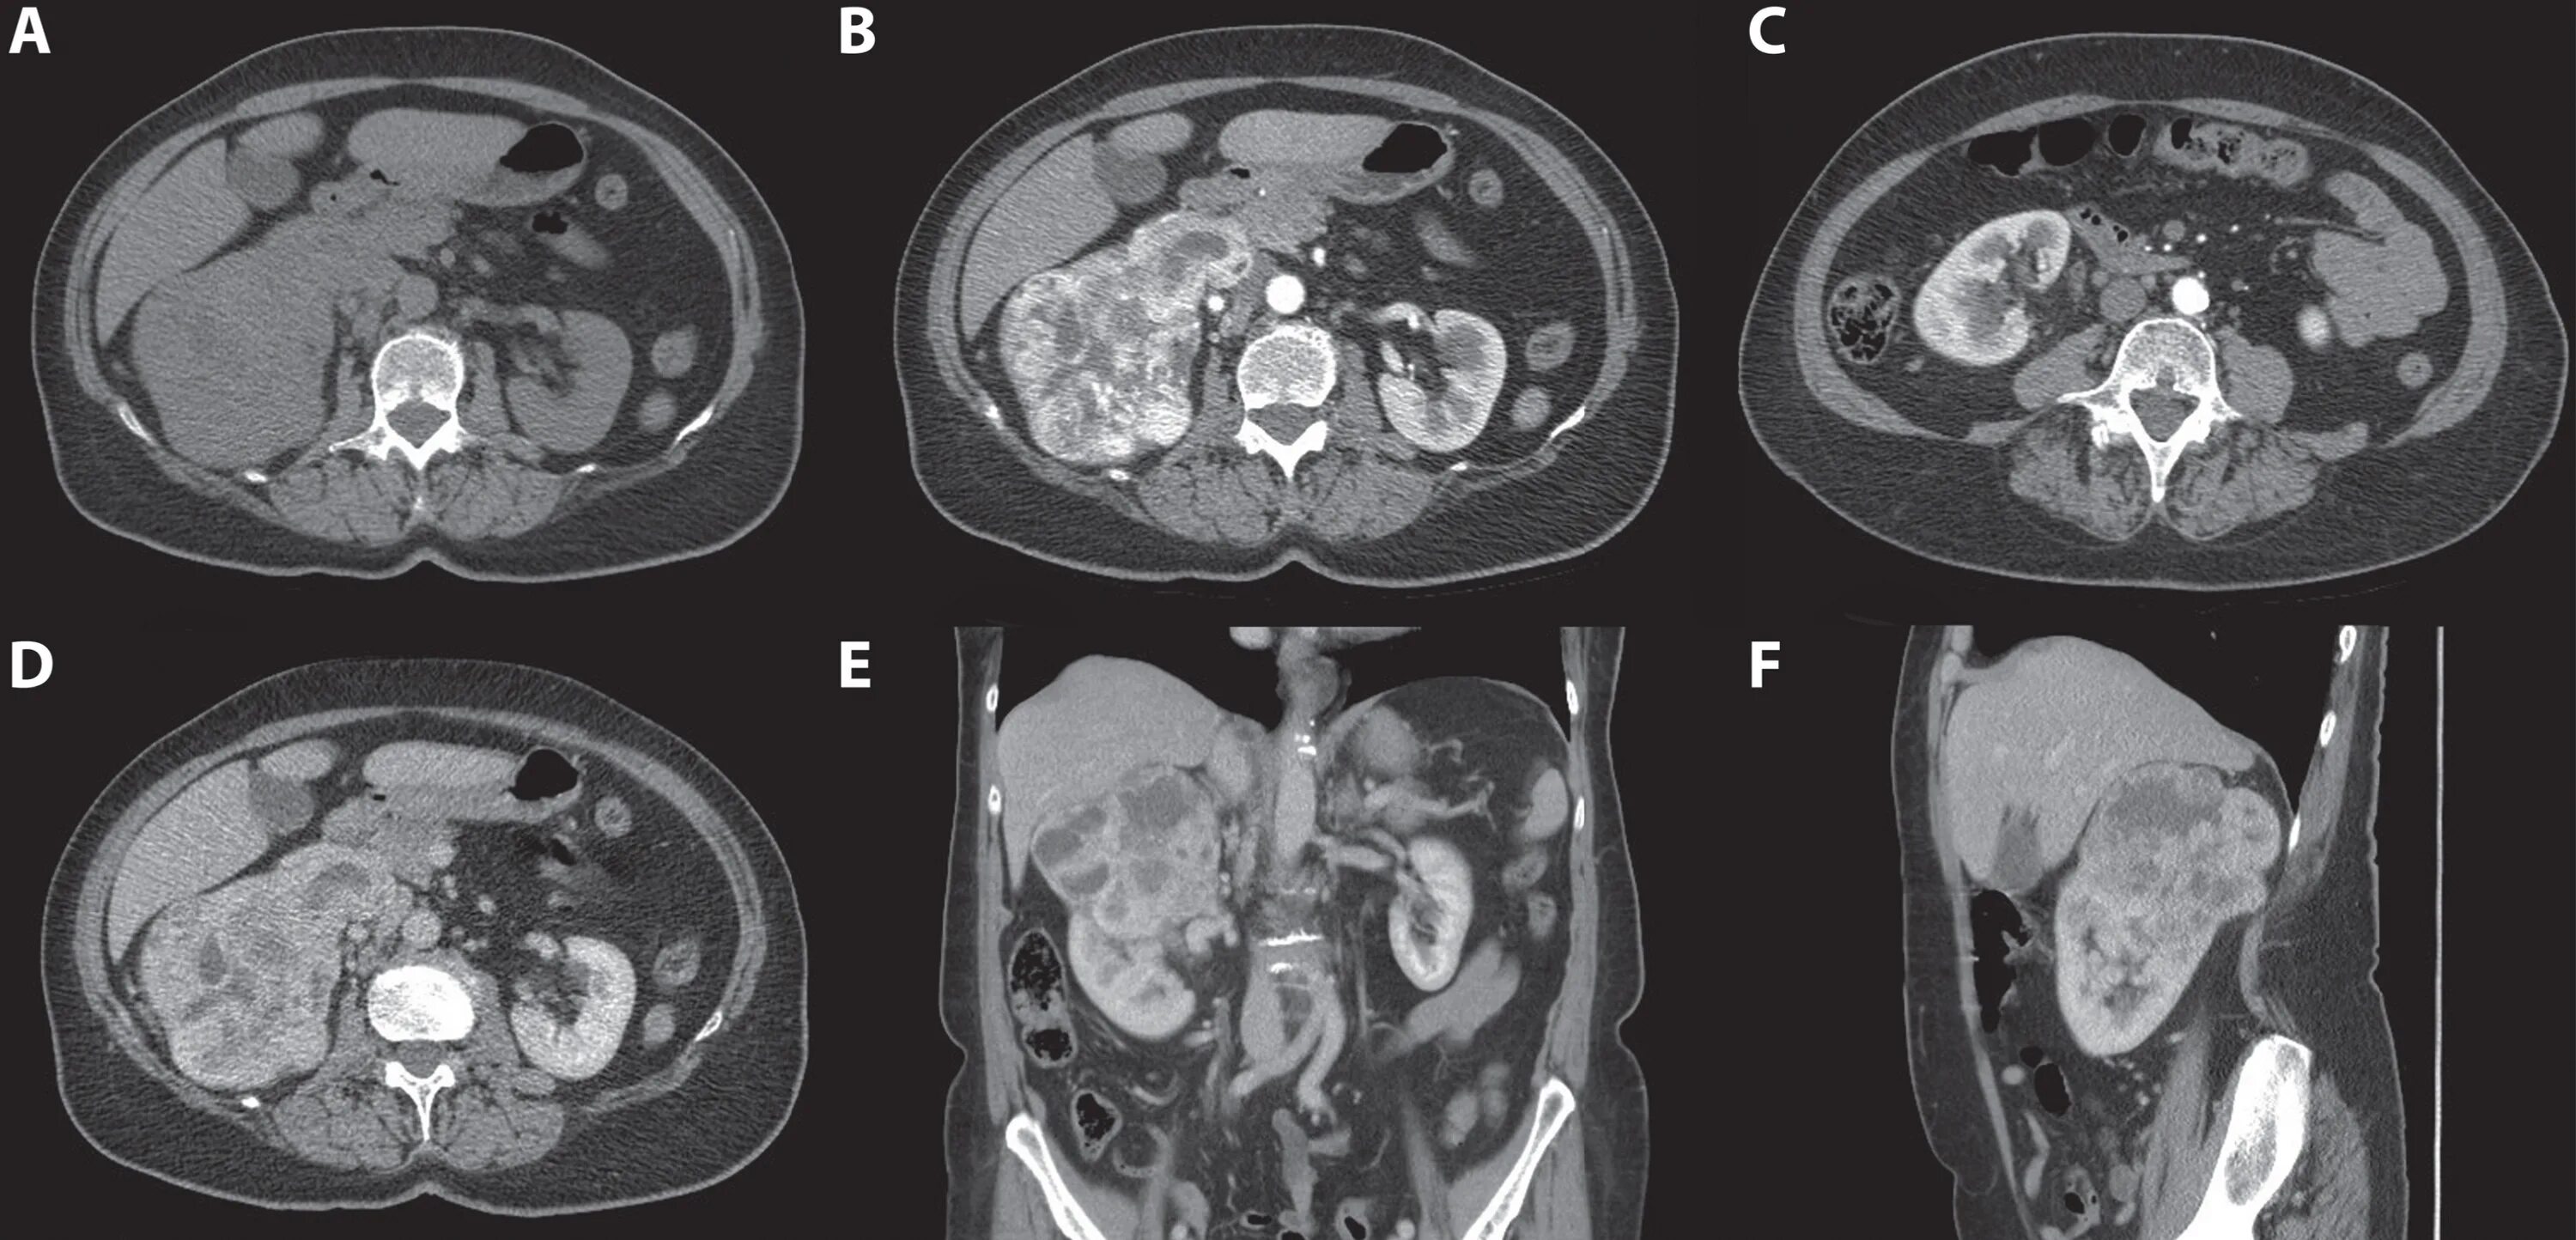

Гиперваскулярное образование почки что это такое